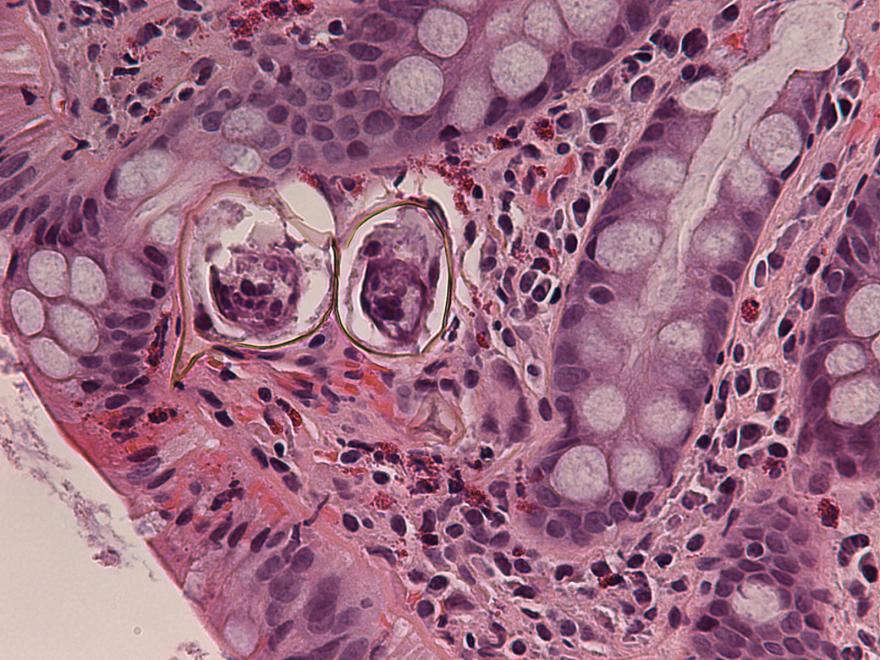

Шистосомоз: что нужно знать о паразитах